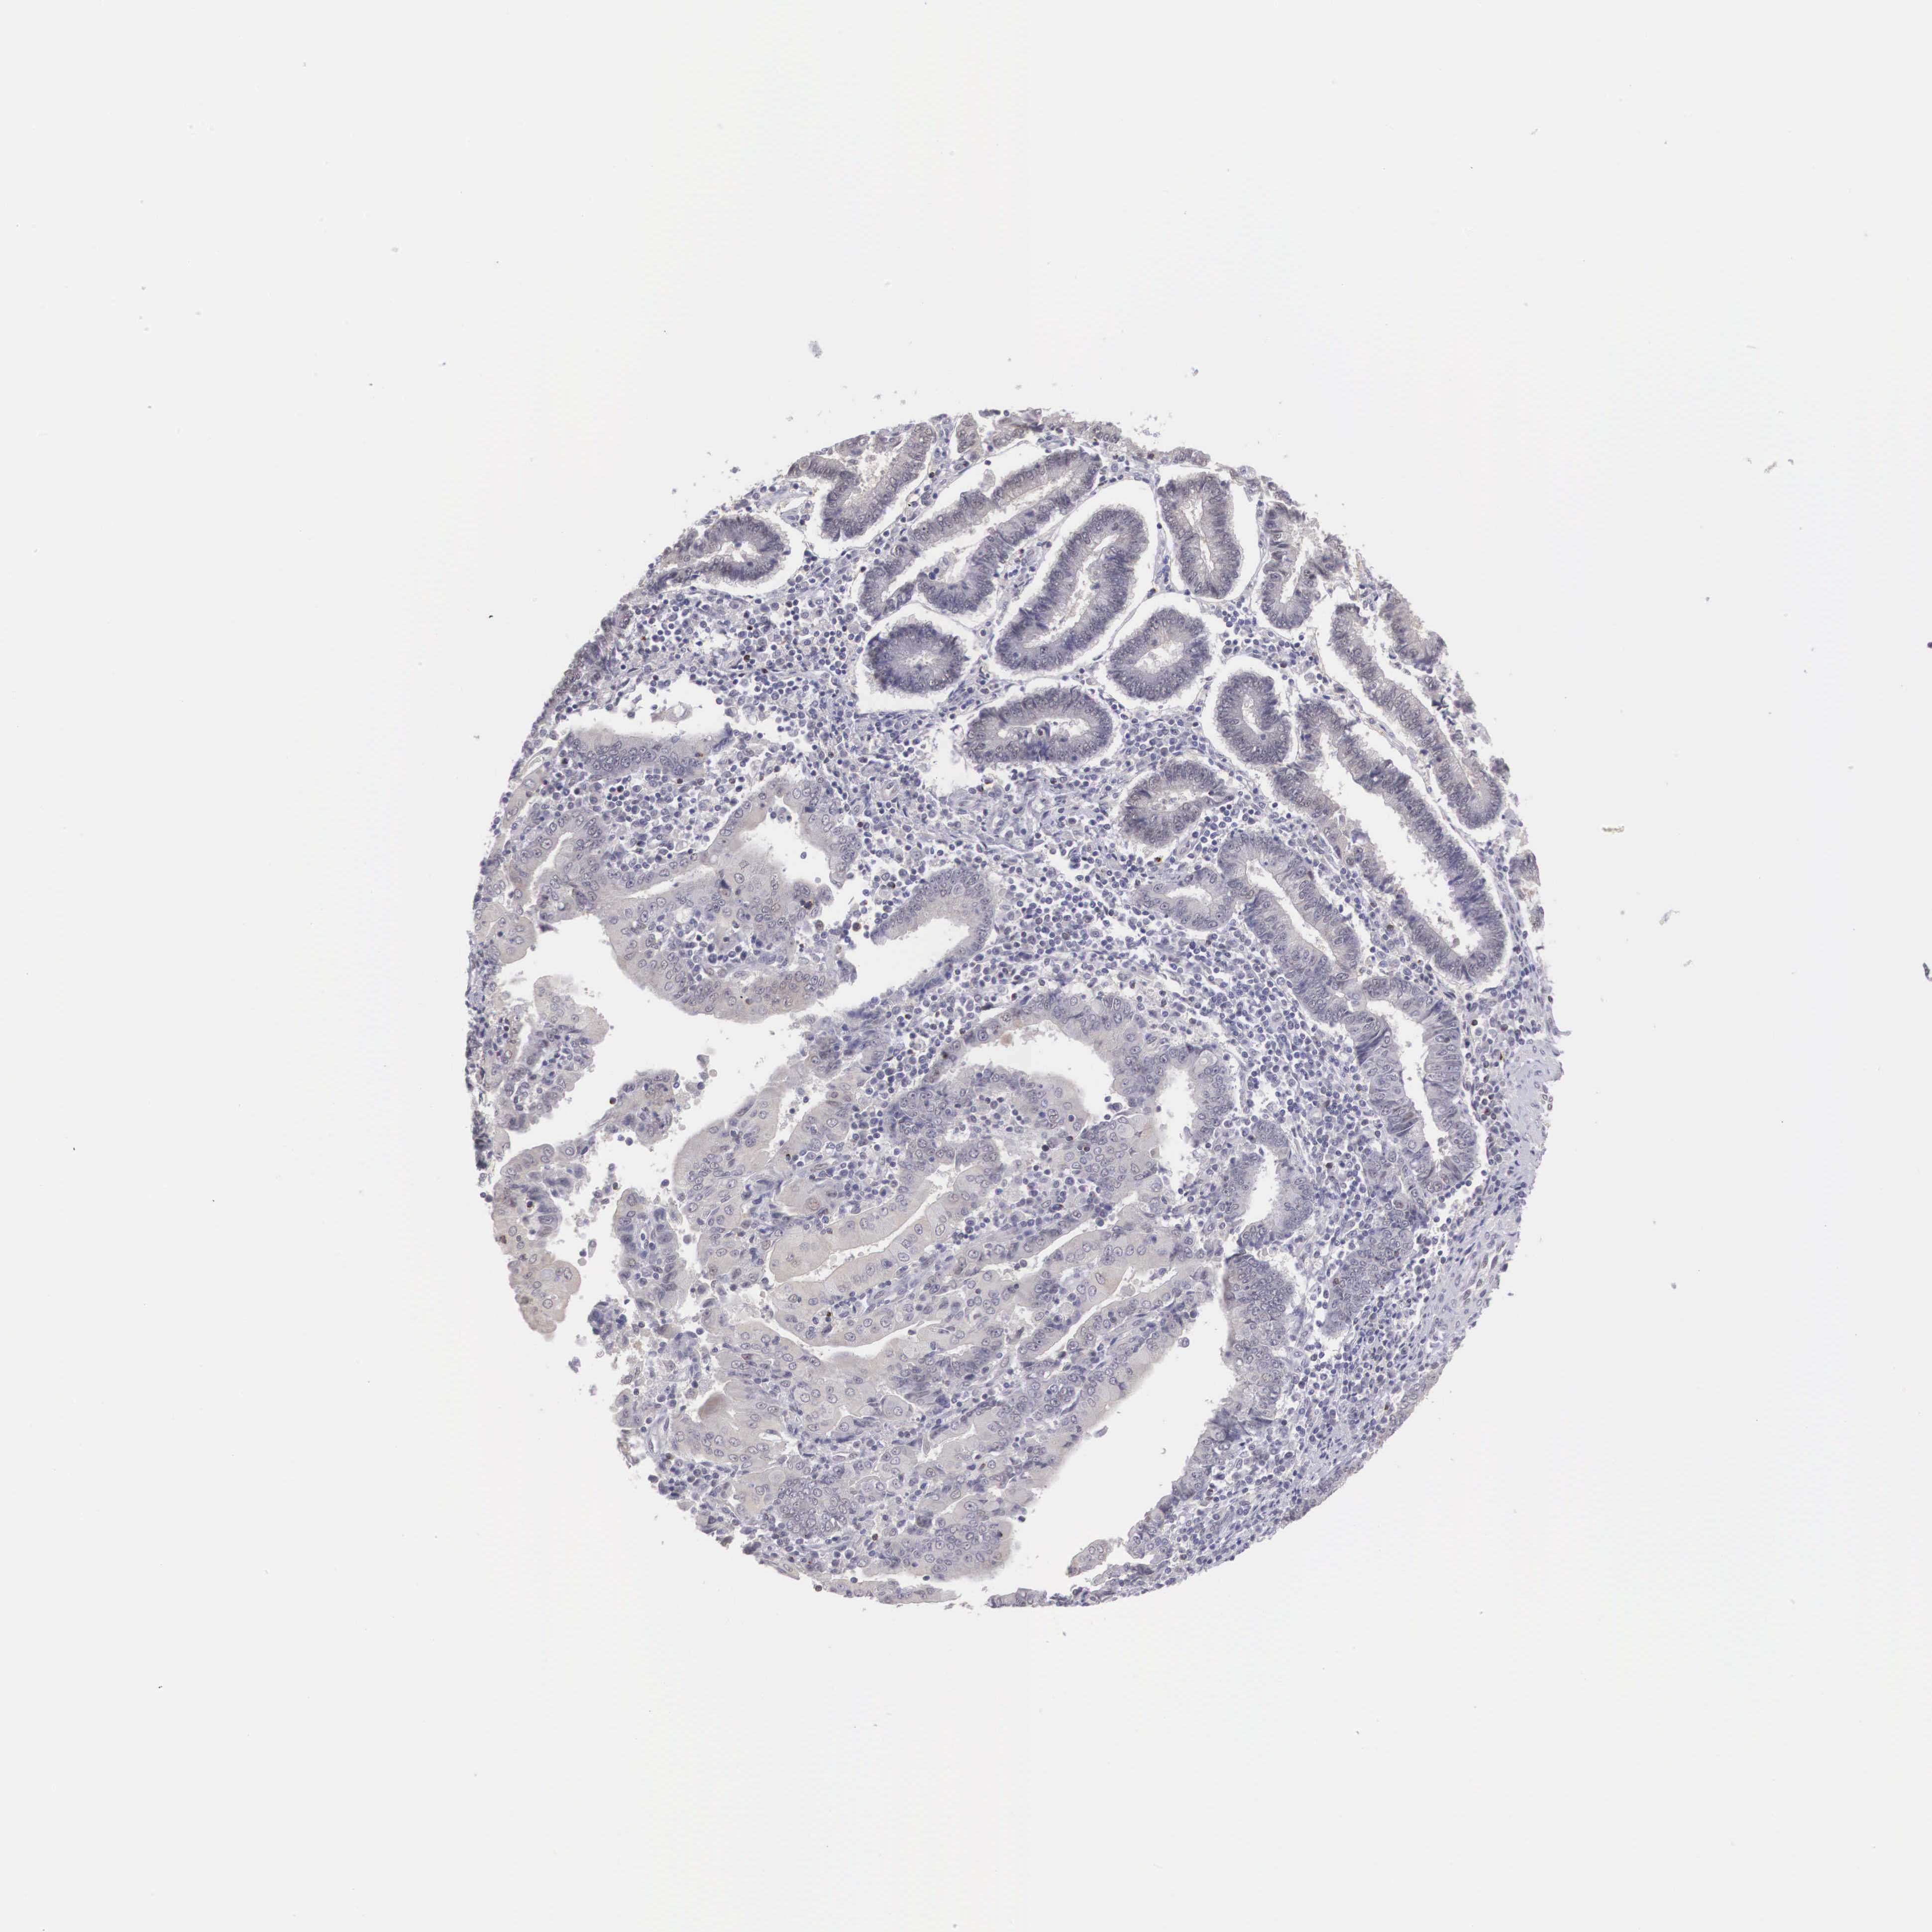

ENDOMETRIAL CANCER - Protein expressioni

A mouse-over function shows sample information and annotation data. Click on an image to view it in a full screen mode. Samples can be filtered based on level of antibody staining by selecting one or several of the following categories: high, medium, low and not detected. The assay and annotation is described here.

Note that samples used for immunohistochemistry by the Human Protein Atlas do not correspond to samples in the TCGA dataset.

Antibody stainingi

Antibody staining in the annotated cell types in the current human tissue is reported as not detected, low, medium, or high, based on conventional immunohistochemistry profiling in selected tissues. This score is based on the combination of the staining intensity and fraction of stained cells.

Each image is clickable and will lead to virtual microscopy that enables deeper exploration of all samples and also displays staining intensity scores, fraction scores and subcellular localization as well as patient and tissue information for each sample.

Antibody HPA000686

Staining

High

Medium

Low

Not detected

Intensity

Strong

Moderate

Weak

Negative

Quantity

>75%

75%-25%

<25%

None

Location

Nuclear

Cytoplasmic/membranous

Cytoplasmic/membranous,nuclear

Adenocarcinoma, NOS